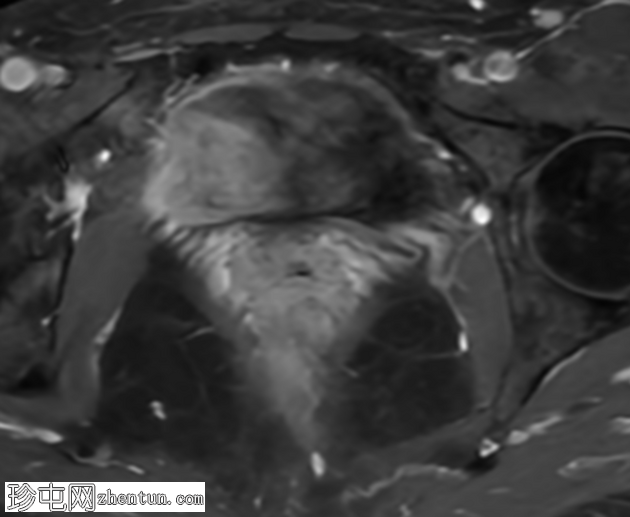

冠状位

T2加权像

盆腔MRI显示右侧卵巢解剖位置可见一边界清晰的卵圆形肿块。该病灶由囊性和实性成分组成。囊性部分壁薄,在T2加权像上呈均匀高信号,在T1加权脂肪抑制序列上呈低信号,无对比剂增强。该实性成分的信号特征与正常卵巢组织相似,DWI成像未见扩散受限,静脉注射造影剂后未见异常强化。

此外,在子宫左侧壁可见一管状薄壁囊性结构,延伸至同侧髂外血管,末端呈盲端。该结构在T2加权像上呈均匀高信号,在T1加权脂肪抑制序列上呈低信号,且无造影剂强化。

双侧附件区未见病理性扩散受限。子宫大小及信号强度正常,子宫内膜增厚正常。膀胱未见异常。未见盆腔淋巴结肿大或游离液体。

本例中,盆腔MRI显示,患者右侧卵巢解剖位置存在一个边界清晰的附件肿块,该患者有20年前行双侧输卵管卵巢切除术的病史。该病灶包含囊性和实性成分,其中实性部分表现出与正常卵巢组织相似的信号特征。无扩散受限和无可疑的增强扫描强化提示排除恶性病变。这些影像学特征结合相关的手术史进行解读,符合残留卵巢组织的特征,支持卵巢残留综合征的诊断。此外,还发现对侧子宫左侧延伸出一个管状薄壁囊性结构,末端呈盲端。其形态、信号特征和无强化表现符合输卵管残端或输卵管残端积水,这是输卵管切除术后常见的术后表现。附件残余的存在进一步支持术后病因,而非原发性妇科肿瘤